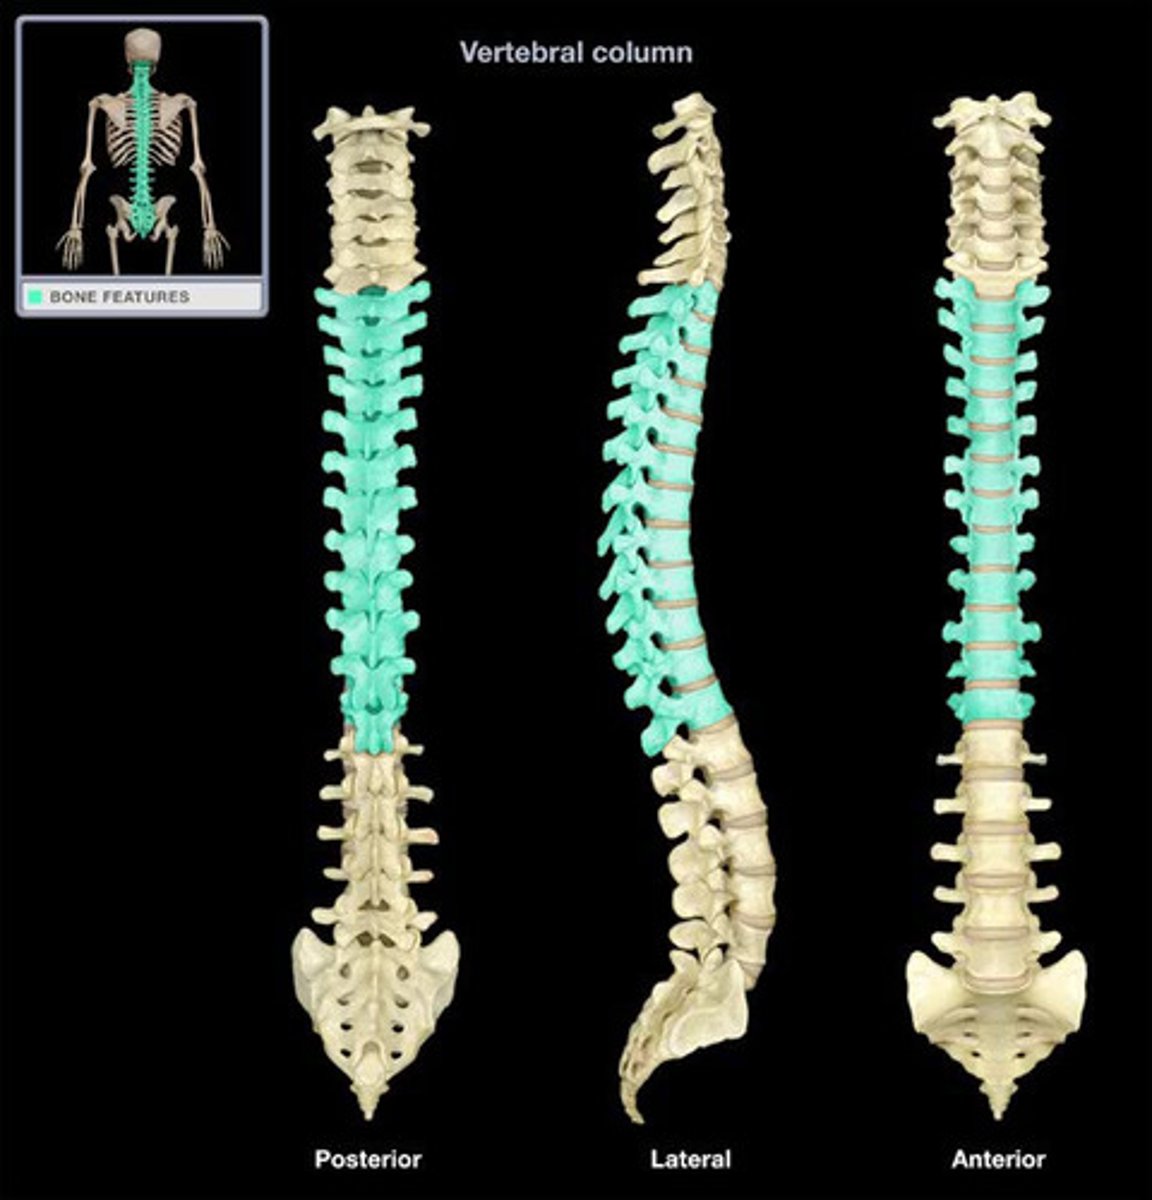

Cervical Vertebrae 7

Thoracic Vertebrae 12

Lumbar Vertebrae 5

Sacrum 5 fused

Coccyx 3-5